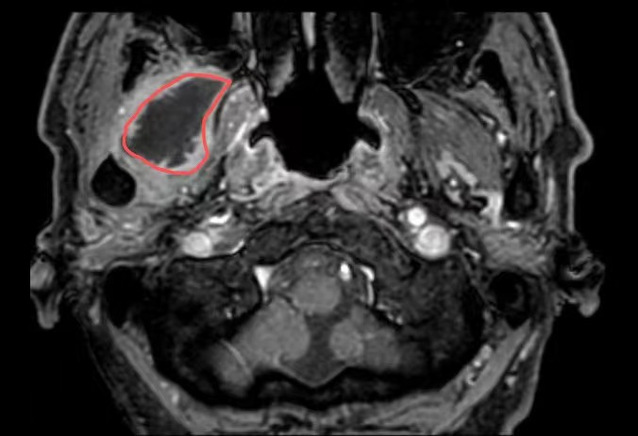

在亚洲色吧 超声介入科,徐斌主任就接诊了这样一位患者。一个月前,患者熊先生脸颊部隐隐作痛,到医院一查是牙齿发炎了,抗炎后熊先生拔除了发炎的牙齿。但是,回家后没几天,面颊部就又开始疼痛、发热。经过反复就医、检查、消炎止痛后做增强磁共振提示:右翼外肌及颞肌异常信号,考虑脓肿可能,相关科室的医生和熊先生说这个手术可能比较复杂,需要行开放性手术。

△磁共振提示病灶(红圈处)